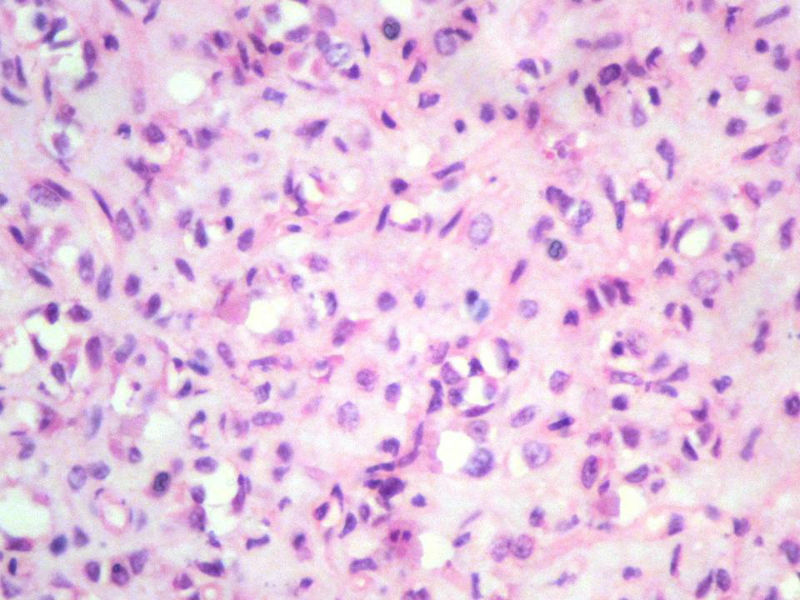

男,27岁,右股骨上段皮下肿物1年余,无明显疼痛,检查肿物明显隆起于皮下,边界清楚,手术完整切除肿物。肉眼,肿物6X6X5厘米,外观多结节状,似有包膜,切面灰白色,质韧。

特别提示:镜下核分裂3-4/HP.

1. 本例没有做KI-67,但我在前面特别提示:镜下核分裂3-4/HP.

3. 本例组织学改变与粘液性脂肪肉瘤,粘液样纤维肉瘤,纤维粘液样肉瘤,骨外粘液样软骨肉瘤都有重叠之处,且镜下并未见典型结构。由此,免疫组化结果就尤显重要。特别是专业书籍提到,突触素或嗜铬素阳性,对鉴别诊断有重要意义。我用CGA,也是在以上几个肿瘤中举棋不定而为。NSE和CK没用,其实我想用更多的抗体来证实更多的东西,但患者的经济条件不太好,遗憾!